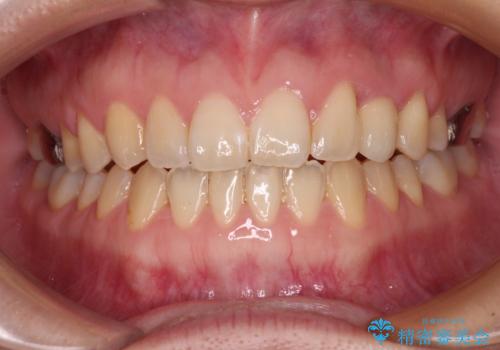

受け口で開咬を急速拡大装置とインビザラインで改善 欠損部分はインプラントにて補綴治療

矯正治療が終わるタイミングに合わせてインプラントの埋入を行っていたので、矯正治療を終了すると同時にセラミック補綴治療を行えました。

インビザラインの装着時間が不十分であったので、治療期間は長期間となりました。